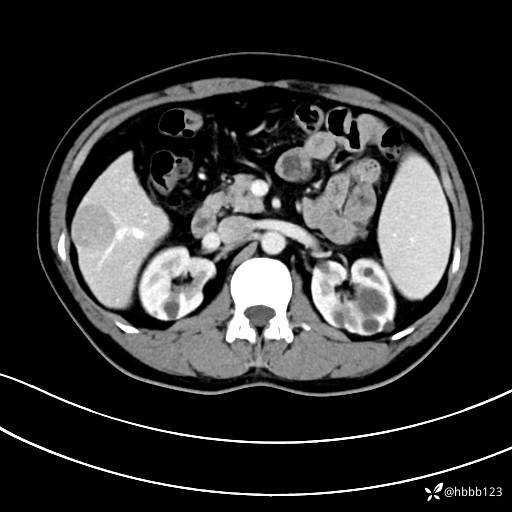

门诊完善上腹部CT平扫+增强。

平扫: